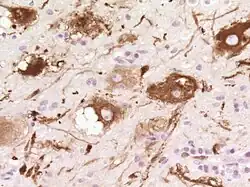

Auf zellulärer Ebene sieht man dysplastische (hypertrophe und später blasig aufgetriebene, vakuolisierte) Purkinjezellen. Die Schichtung des Kleinhirns ist umgekehrt (invertiert) und die Körnerzellschicht ist weitgehend aufgelöst.